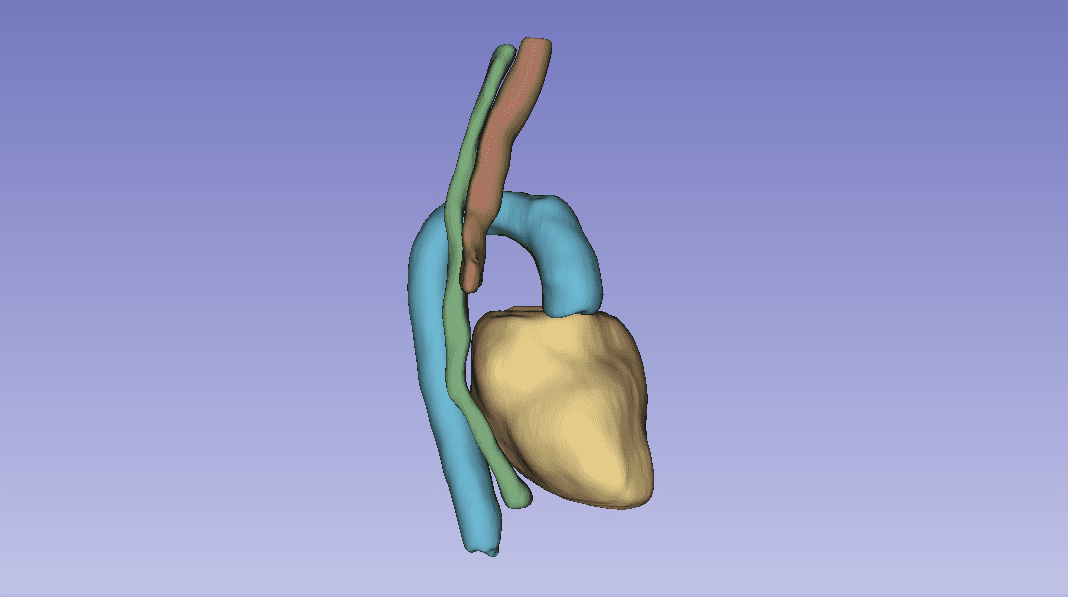

Overview

Group project for AI for Medical Imaging (UvA, part of the VU M.Sc. AI program) on the SegTHOR challenge: segmenting four thoracic organs (heart, esophagus, trachea, aorta) from 3D CT volumes. We compared a 2D baseline (ENet), a custom 2D architecture (CustomNet, U-Net based), and 3D Full-Resolution nnU-Net.

Before any modelling, the heart annotations were misaligned for several patients. Patient 27 had two ground truth files in the dataset, one correct and one misaligned. We tried to fix the misalignment with Elastix (rigid + affine transformations), but no parameter combination got the heart to register cleanly.

The fix that worked was a centroid-then-rotation approach: subtract the misaligned heart's centroid from the correct centroid to get a translation vector, then sweep rotation angles in the transverse plane and pick the one that maximised IoU. The optimal correction was a −26.6° rotation around the superior-inferior axis. We then applied the same transformation across the dataset.